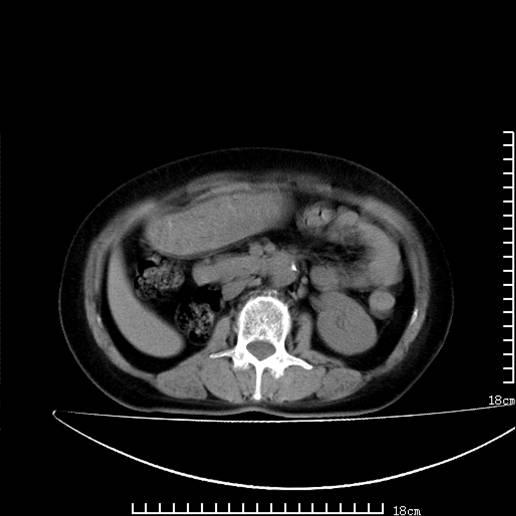

以下是引用pujunzhi在2008-5-30 15:31:00的发言:[br]异位肾—盆腔肾。当看到肾窝无肾脏时,要想到孤立肾和异位肾,异位肾最常见是盆腔肾,偶见胸腔,易误认为肺占位,只要想到就不会漏诊。建议增强扫描。